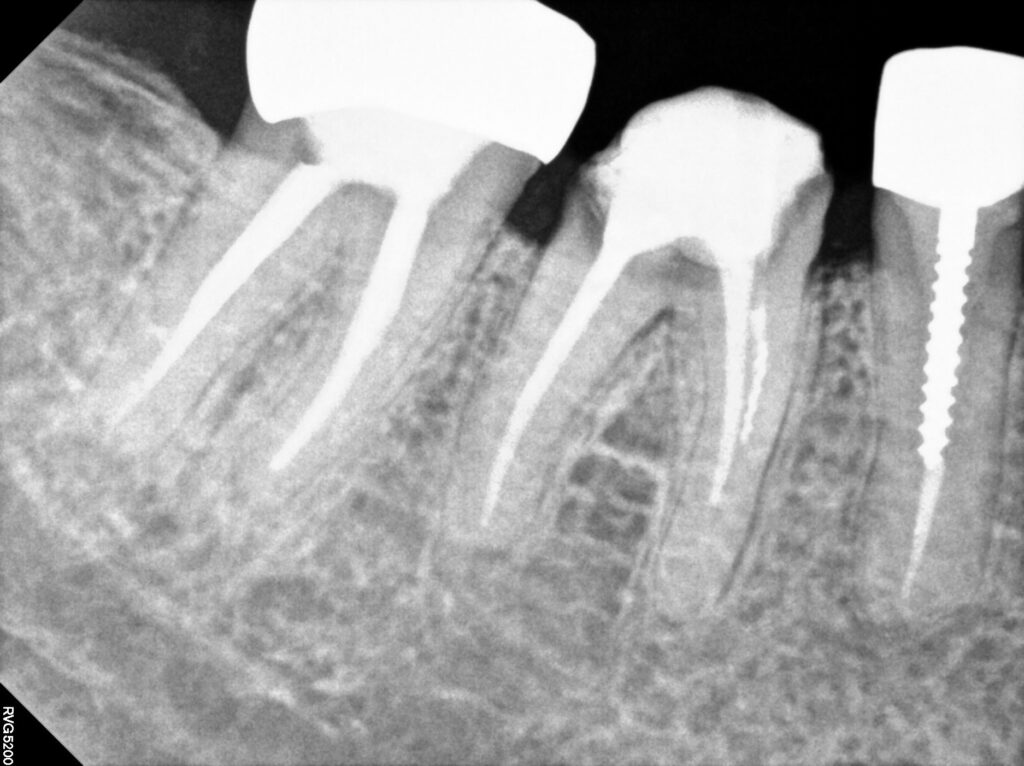

엑스레이 상에서도..

치아 뿌리가 너무 짧고

이차 충치도 있고

심지어 크라운을 만들어 낼 페룰 확보도

어려울 것 같습니다..